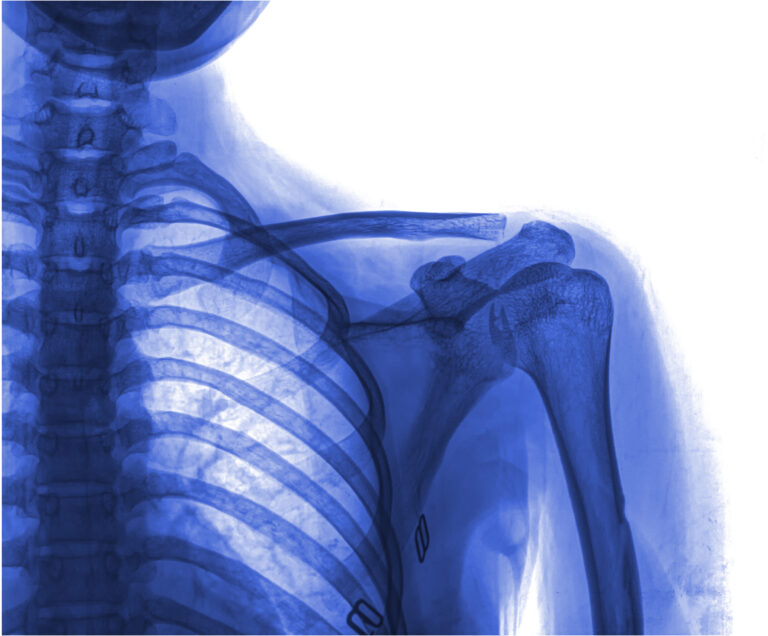

Distal clavicle resection is a procedure where a portion of the clavicle (collar bone) near the acromioclavicular joint (part of your shoulder joint) is removed to relieve the effects